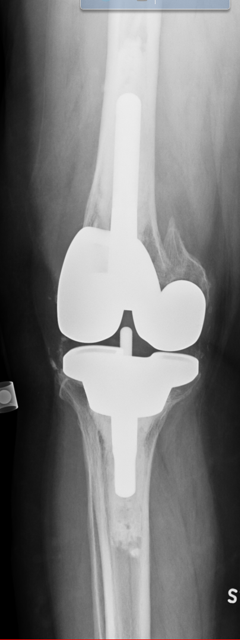

Case: 69 yo M w/ hx of left TKA w/ revision x 2 for aseptic loosening. Now with acute worsening left knee pain. Progressive radiolucent lines about femoral stem, change in modular junction appearance. Operative plan? How to address sclerotic canal of multiply revised knee?

4

Metallic stained soft tissue on approach. Modular junction failure. Stem and cement mantle removed en bloc. Pt underwent impaction bone grafting of polished/sclerotic canal. Cemented femoral stem with cone. https://t.co/hyA3fGNxF5

0